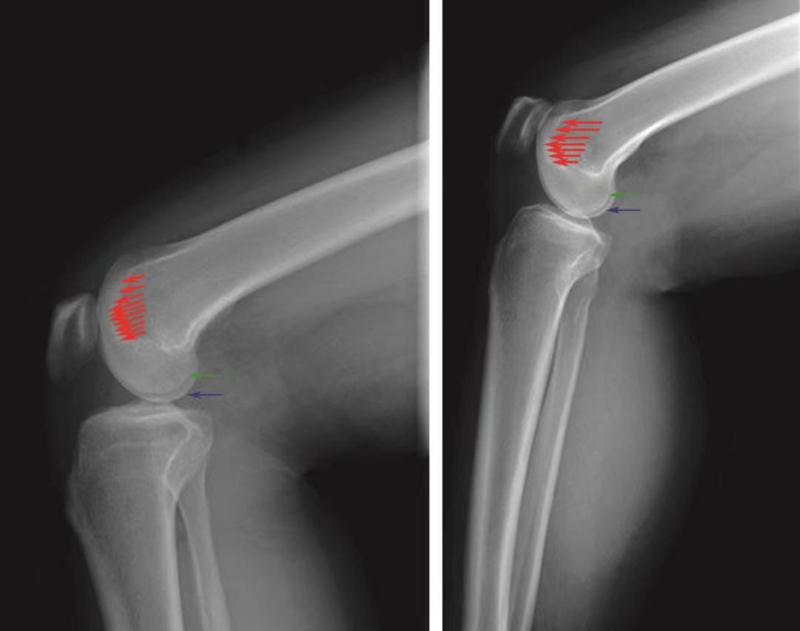

在标准的X线侧位片上,正常的膝关节滑车形态有以下3个特点(图10):①Blumenssat线延续为股骨滑车沟基底线,该基底线始终位于股骨髁轮廓线的后方,意味着股骨滑车沟低于股骨滑车的侧壁;②滑车沟基底线的最高点不超过股骨干前方皮质的延长线;③股骨内外滑车轮廓线几乎重叠,只显影为一条轮廓线。

图10 正常股骨滑车侧位X线片的特点

滑车沟基底线(红色箭头)位于股骨外髁轮廓线(绿色箭头)和内髁轮廓线(蓝色箭头)的后方和下方;滑车沟基底线的最高点不超过股骨干前方皮质延长线;股骨内外髁轮廓线重叠